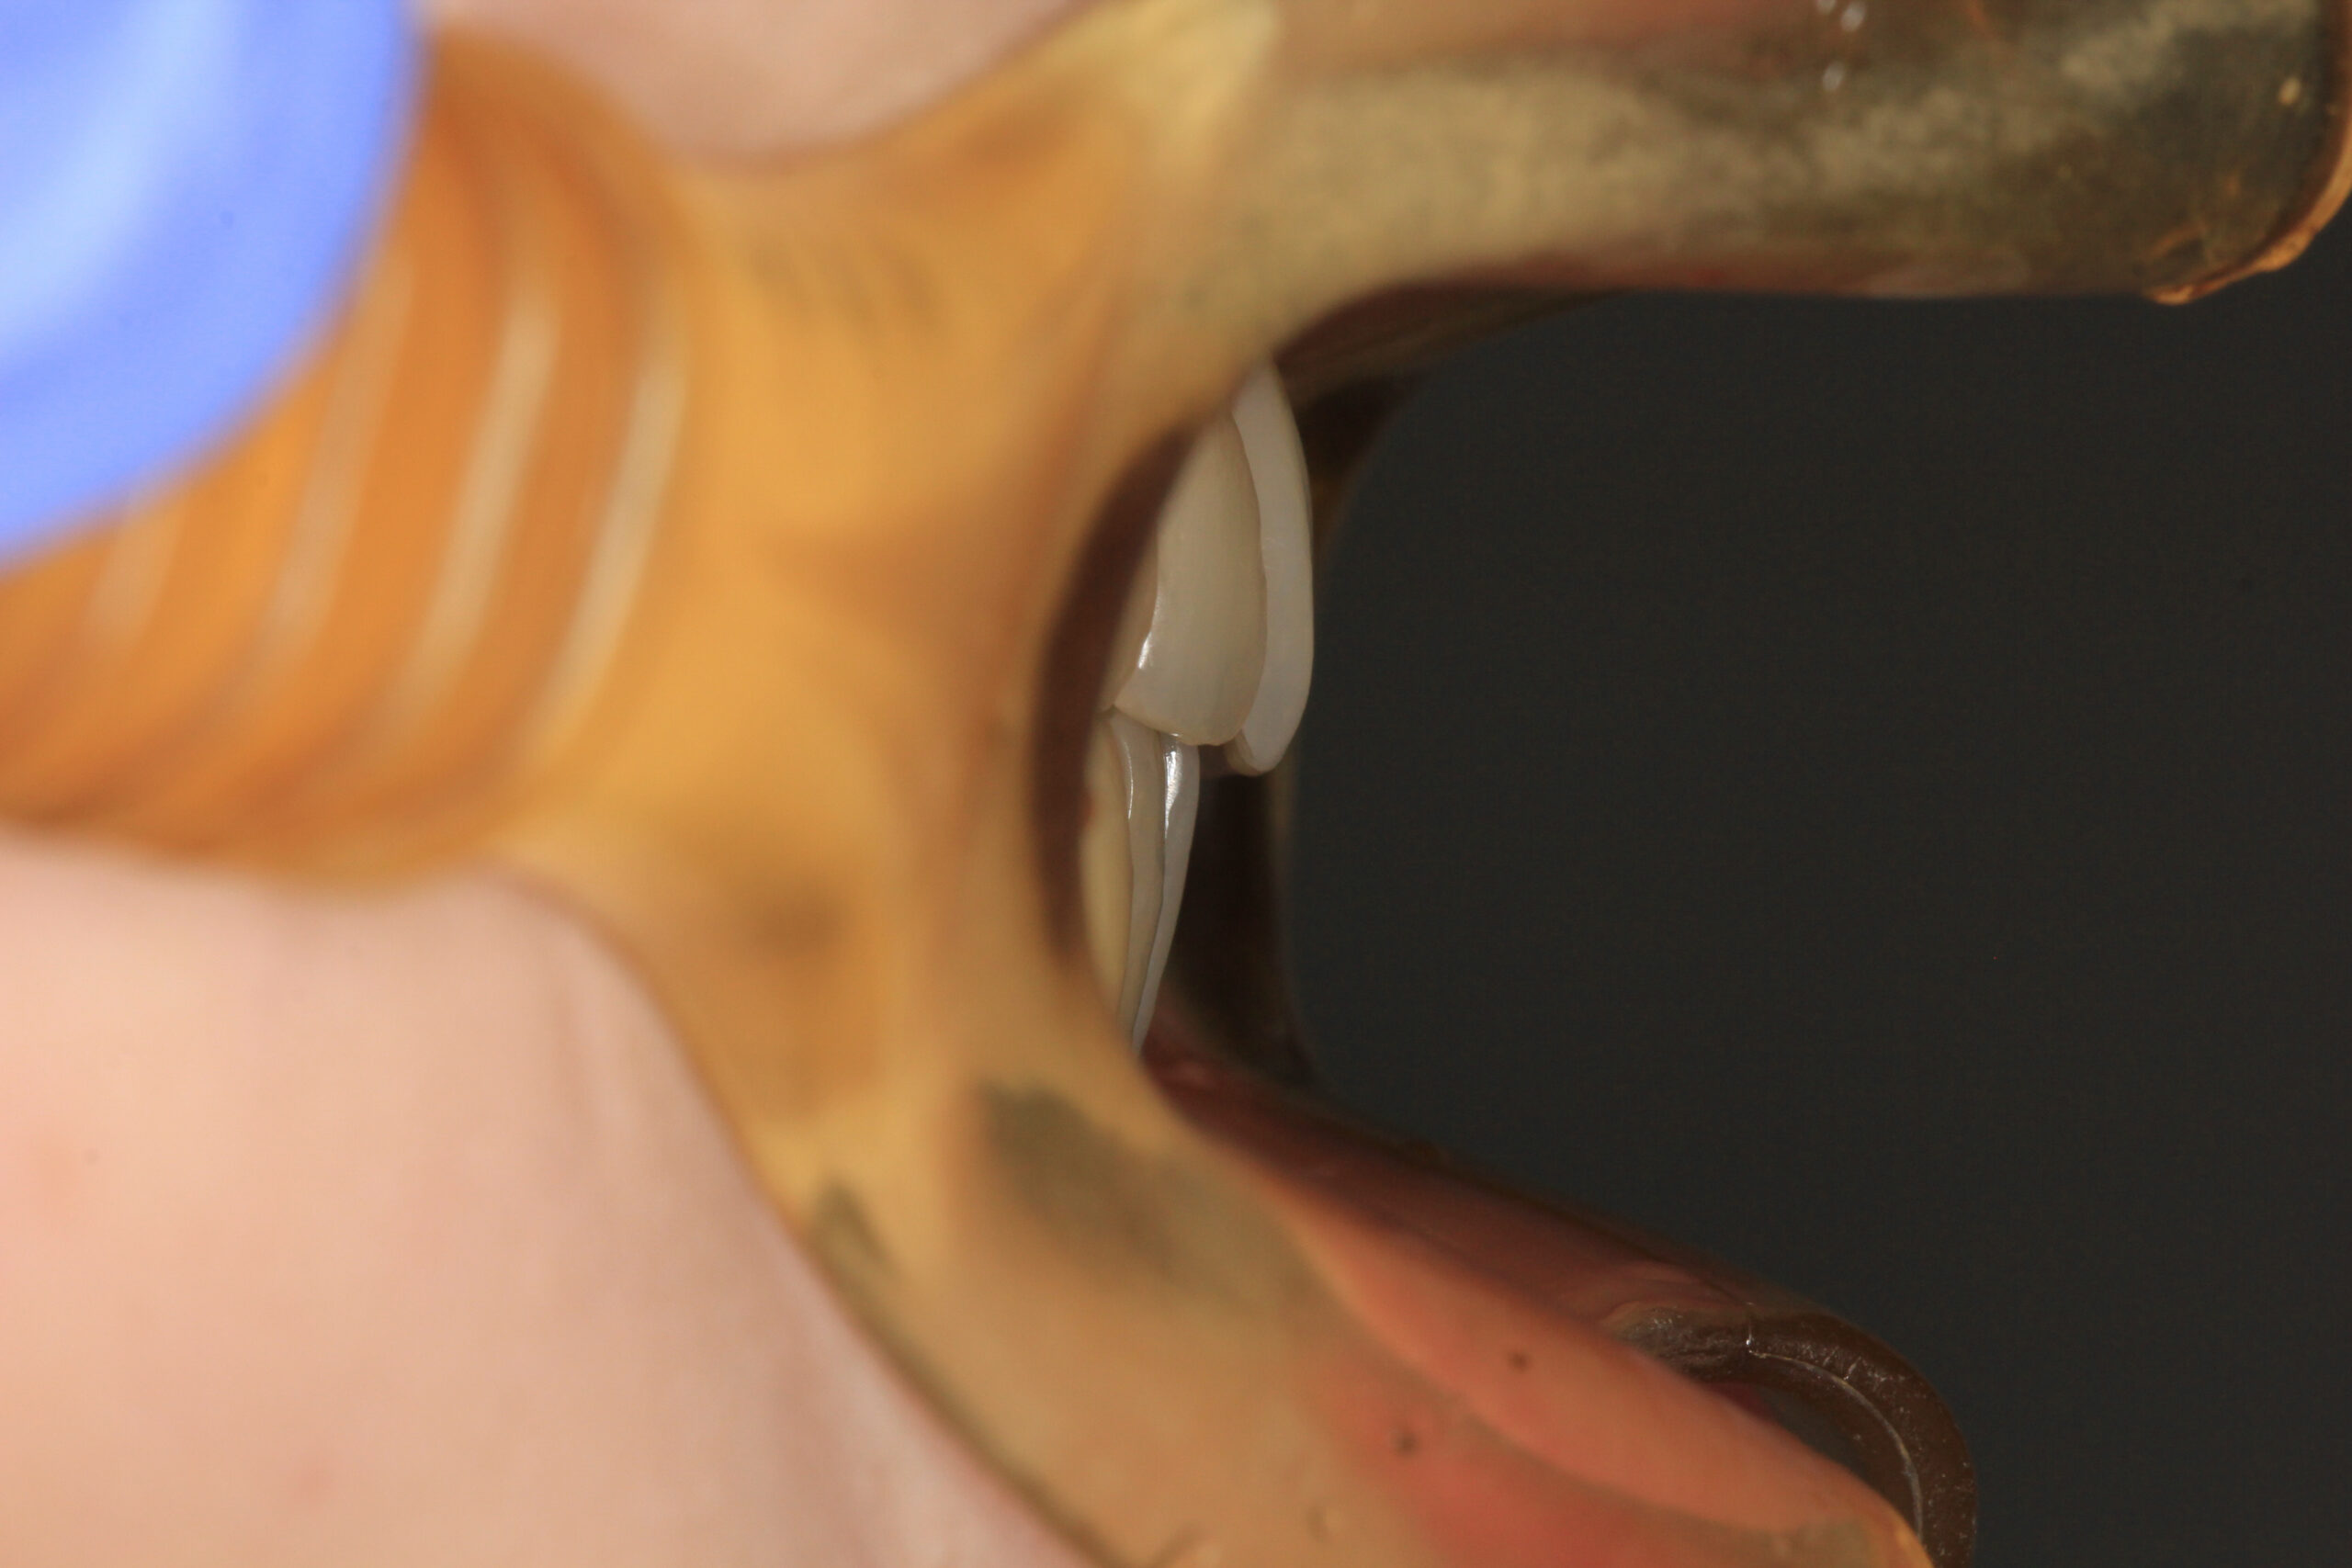

側面観も上顎が出て開咬の状態です。

小臼歯を抜きアーチを広げる事で出っ歯を引っ込めました・

出っ歯も綺麗に引っ込み、開咬も綺麗に改善しました。